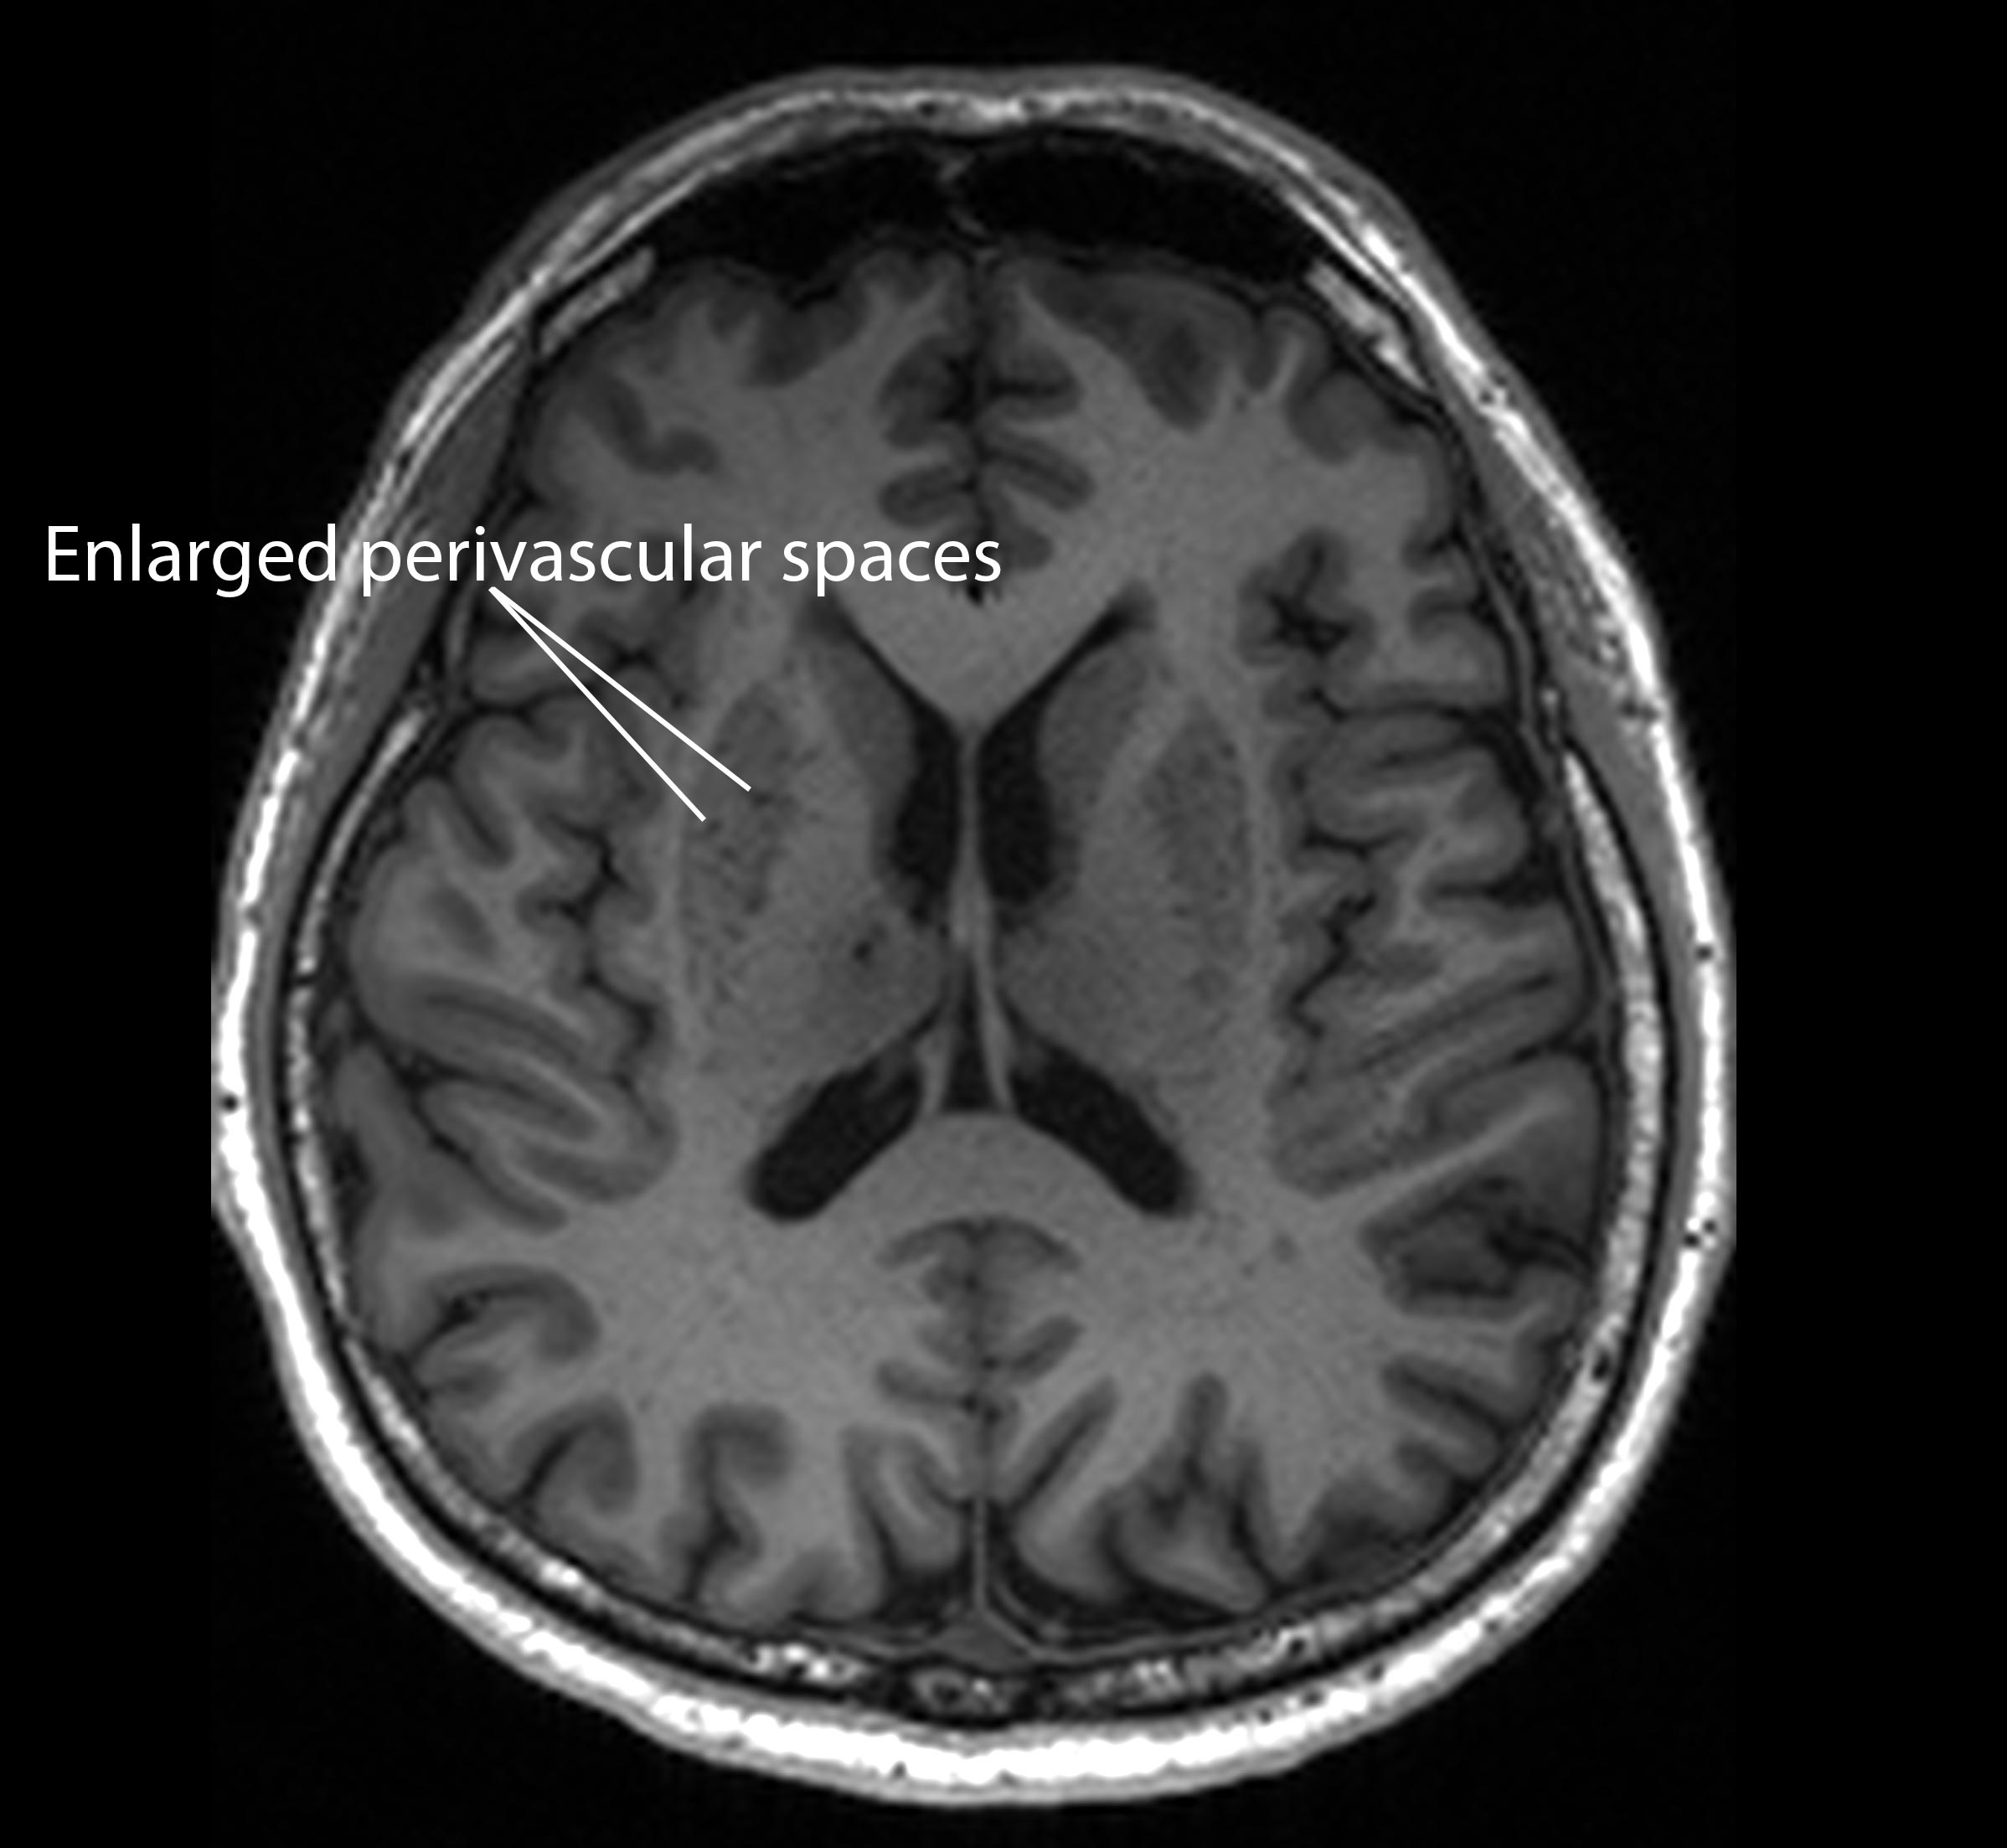

Blocks to these drains, termed “enlarged perivascular spaces”, could serve as an important early signal of dementia, according to the study published in the journal Neurology.

“These brain anomalies can be visually identified on routine magnetic resonance imaging (MRI) scans performed to evaluate cognitive decline,” said neurologist Nagaendran Kandiah from Nanyang Technological University, Singapore (NTU Singapore).

When this drainage system becomes inefficient, these spaces can expand in a way that is detectable on MRI scans, researchers say.

Those with mild cognitive impairment seemed to have clogged drains in their brains, or enlarged perivascular spaces, compared to the other participants, the study found.